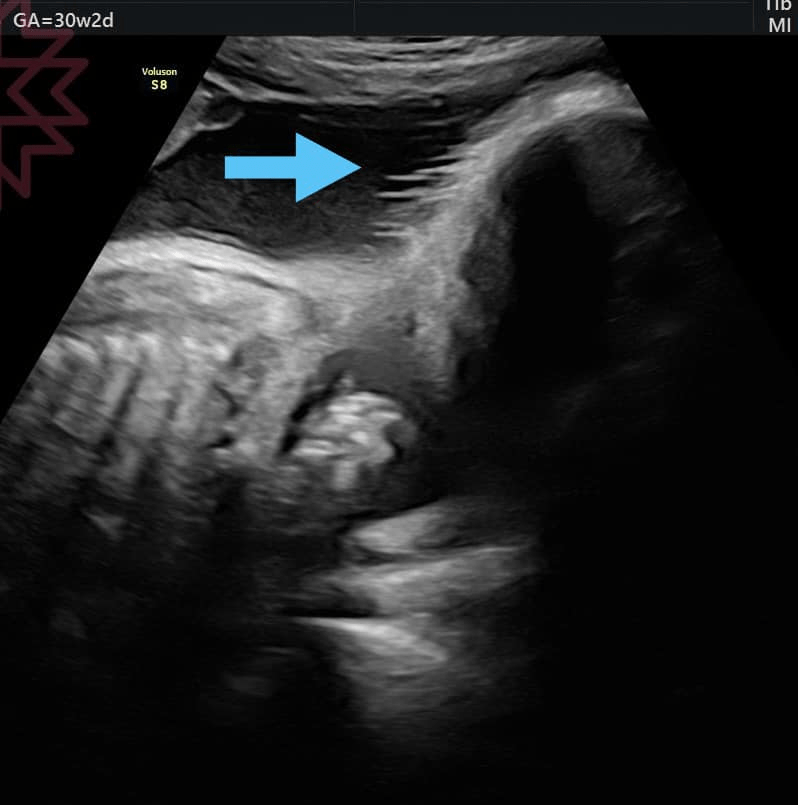

胎兒會有頭髮嗎? 胎兒會有頭髮嗎? 很多媽咪都會很好奇 好啦 其實看得到 只是 很重要嗎?🤷♂️🤣 就醬 =============== 新同學請先參考一下舊文章 很多 我知道 但跟你被洗腦已經一輩子時間的那些迷思比起來 你只需花比你人生短很多很多的時間就可以看完 我們有目錄請動動手指頭滑一下參考置頂文 然後 請善用搜尋🔍功能 所有文章我都也有放在部落格 請google搜尋🔍⋯⋯ 蘇怡寧醫師愛碎念 或是 蘇醫師愛碎念 或者 好像打蘇醫師就會跑出來 你試試😌 然後 請善用裡面的搜尋功能 以上 FB原文討論串 分享此文: 分享到 X(在新視窗中開啟) X 分享到 Facebook(在新視窗中開啟) Facebook 喜歡 正在載入... 相關 在〈胎兒會有頭髮嗎?〉中有 1 則留言 Add yours 引用通告: 蘇醫師愛碎念導覽目錄(置頂文) – 蘇怡寧醫師愛碎念 發表留言 取消回覆 Δ